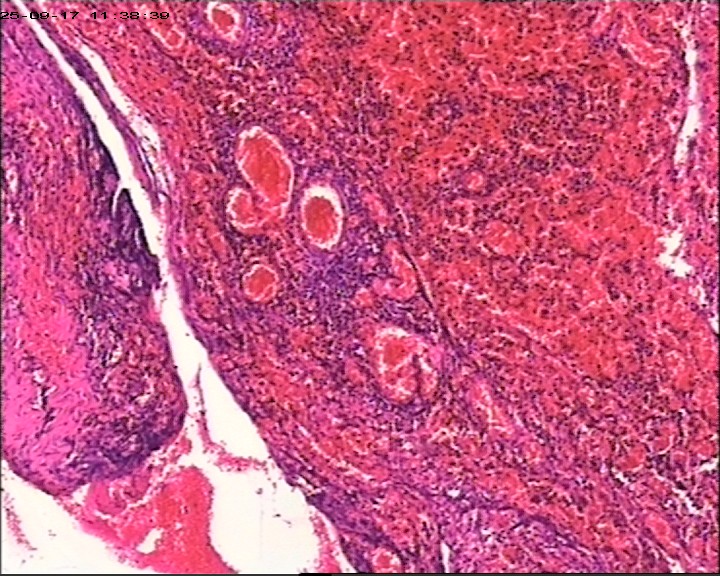

臀部组织,请帮忙看看,谢谢

性别

男

年龄

20岁

临床诊断

一般病史

藏毛窦或囊肿切开术

标本名称

臀部

大体所见

灰白灰黄碎组织一堆,大小为6.5*4*1cm。

描述诊断炎性病变